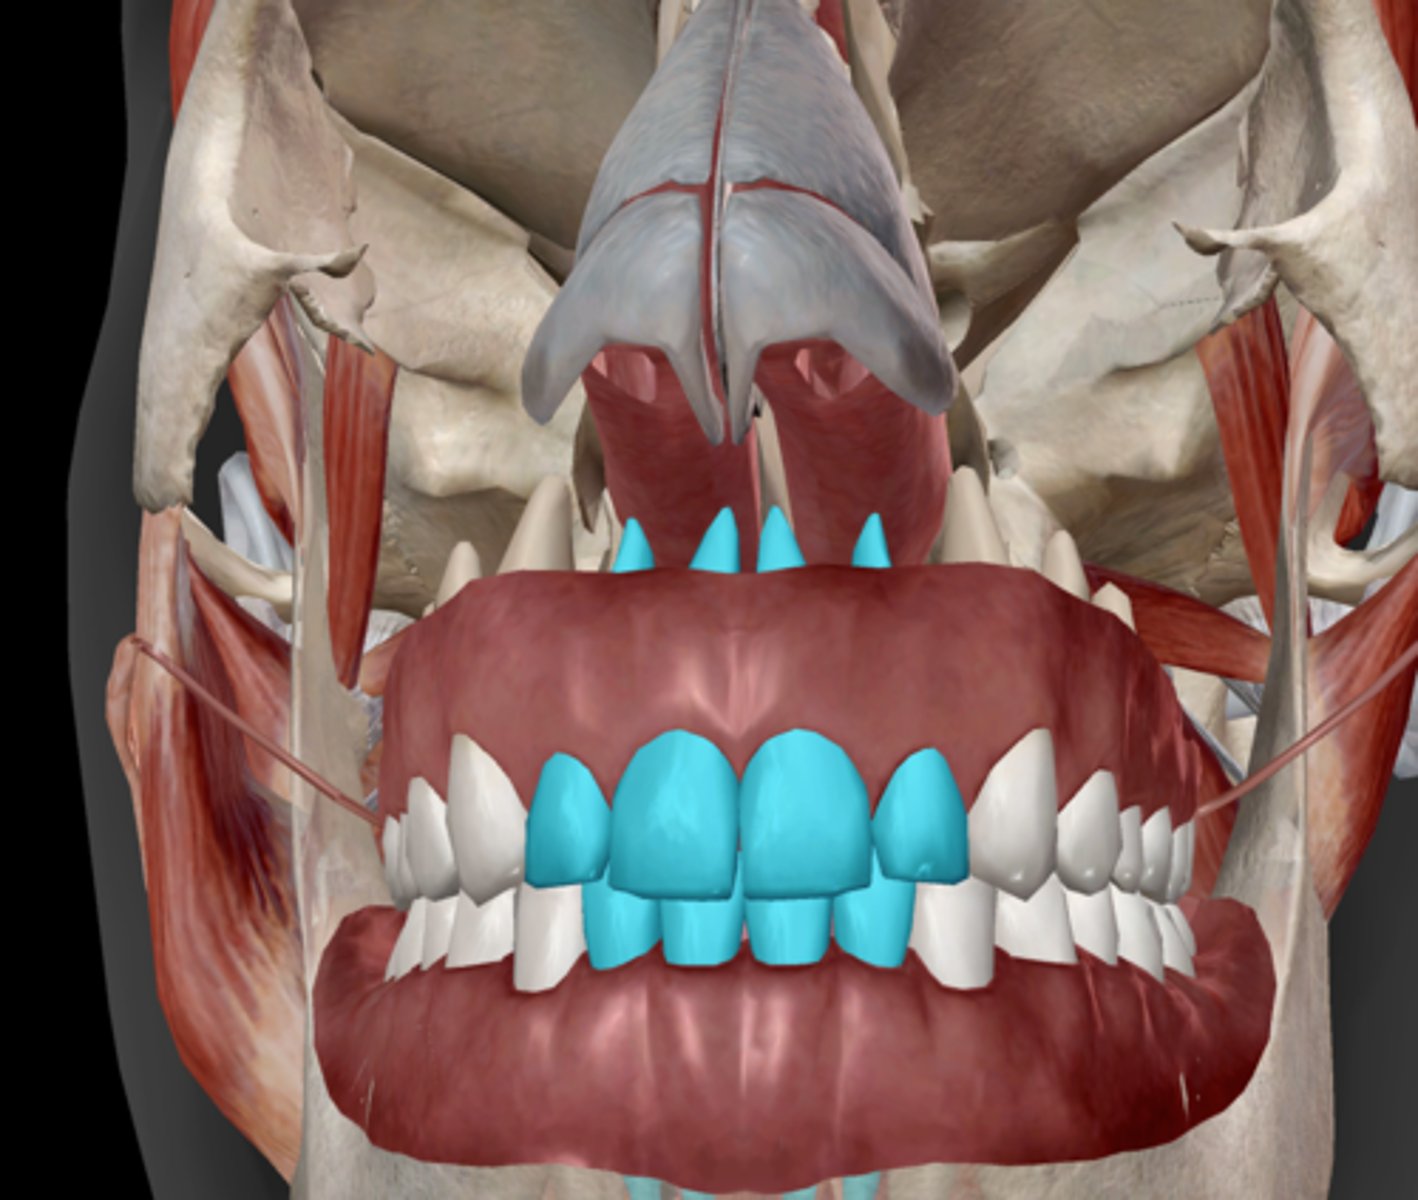

Incisor

Canine (cuspid)

Premolar (bicuspid)

Molars

Tooth structure